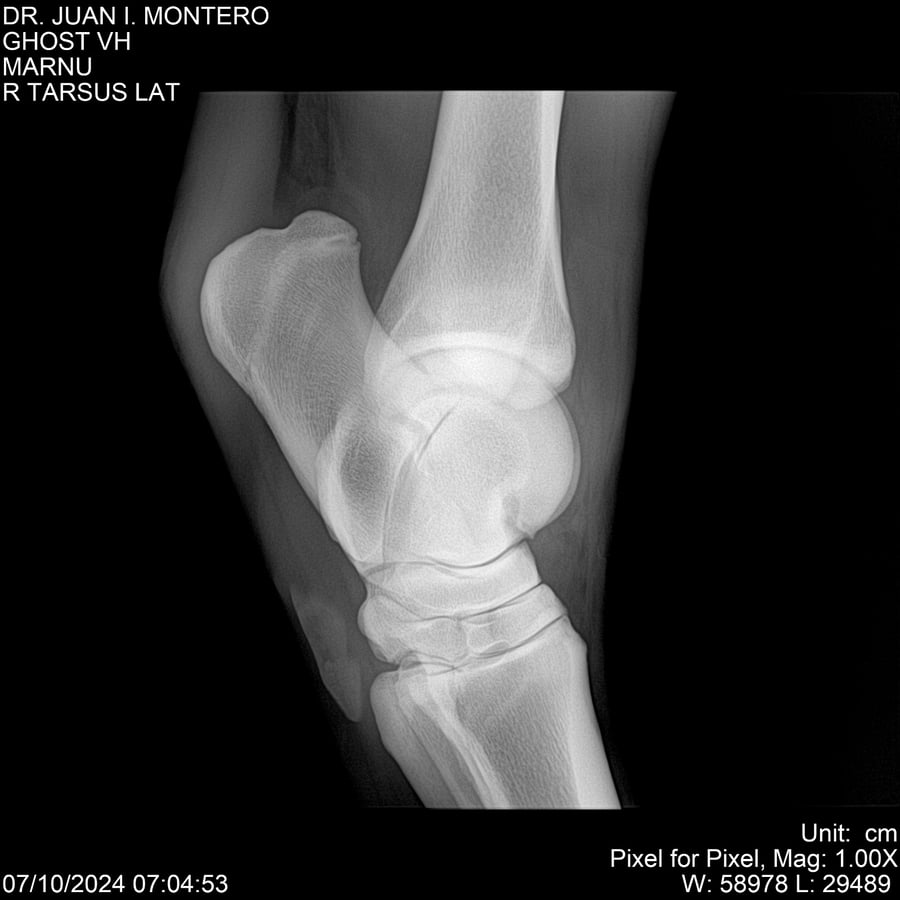

LOTE 15, GHOST VH 🔥 🔥 🔥 Lote Anterior Volver al remate Lote Siguiente Ficha Contacto Montevideo - Ficha del Lote Identificador: #282525 Categoría: Yeguarizos Montevideo - 69 Visualizaciones ClicData Contacto Empresa: Abelenda N. R., Walter Hugo Nombre*: Teléfono* : E-mail* : Mensaje Enviar Registrese gratis Este contenido Exclusivo está disponible sólo para usuarios registrados Ingresar